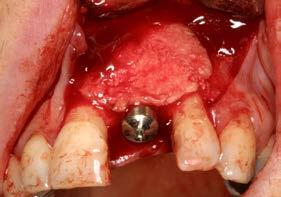

Como primera fase del tratamiento, se procedió a la exodoncia del diente y a la regeneración del alveolo con PRGF-Endoret, tras un legrado minucioso del lecho. Una vez completada esta regeneración, a las 14 semanas

se llevó a cabo la fase quirúrgica para la colocación del implante.

Se elevó un colgajo a espesor total con márgenes amplios (Figuras 4 y 5), lo que permitió recolectar hueso autógeno de las áreas adyacentes mediante un rascador óseo. Este abordaje facilitó además un cierre primario sin tensión tras la colocación del implante y la sobrecorrección. El hueso obtenido se mantuvo en PRGF-Endoret,

Figuras 4 y 5. Elevación del colgajo, donde se aprecia el lecho alveolar regenerado y la zona donante situada por encima del ápice del diente 11.

fracción 2 sin activar, hasta el momento de su utilización en la zona receptora, preservando la vitalidad celular y mejorando la manejabilidad del injerto particulado (Figura 6). Posteriormente, este hueso se unió al recolectado durante el fresado biológico del lecho.10

El lecho implantario se preparó mediante fresado biológico, ajustado al tipo de hueso y a las dimensiones del implante planificado. A continuación, se procedió a la inserción del implante, que alcanzó un torque de inserción adecuado, permitiendo dejarlo en fase de cicatrización con el pilar

correspondiente colocado. Una vez colocado el implante y el pilar de cicatrización, se realizó una técnica de sobrecorrección vestibular con el injerto particulado inmerso en PRGF-Endoret, recubriendo toda la zona con una membrana autóloga de fibrina (fracción 1 activada y retraída). Se suturó con monofilamento no reabsorbible, sin tensión, para evitar el colapso del volumen vestibular que se buscaba ganar (Figuras 7 a 10). Como provisional se empleó el propio diente de la paciente, ferulizado a los adyacentes con resina, a modo de puente Maryland (Figura 11).